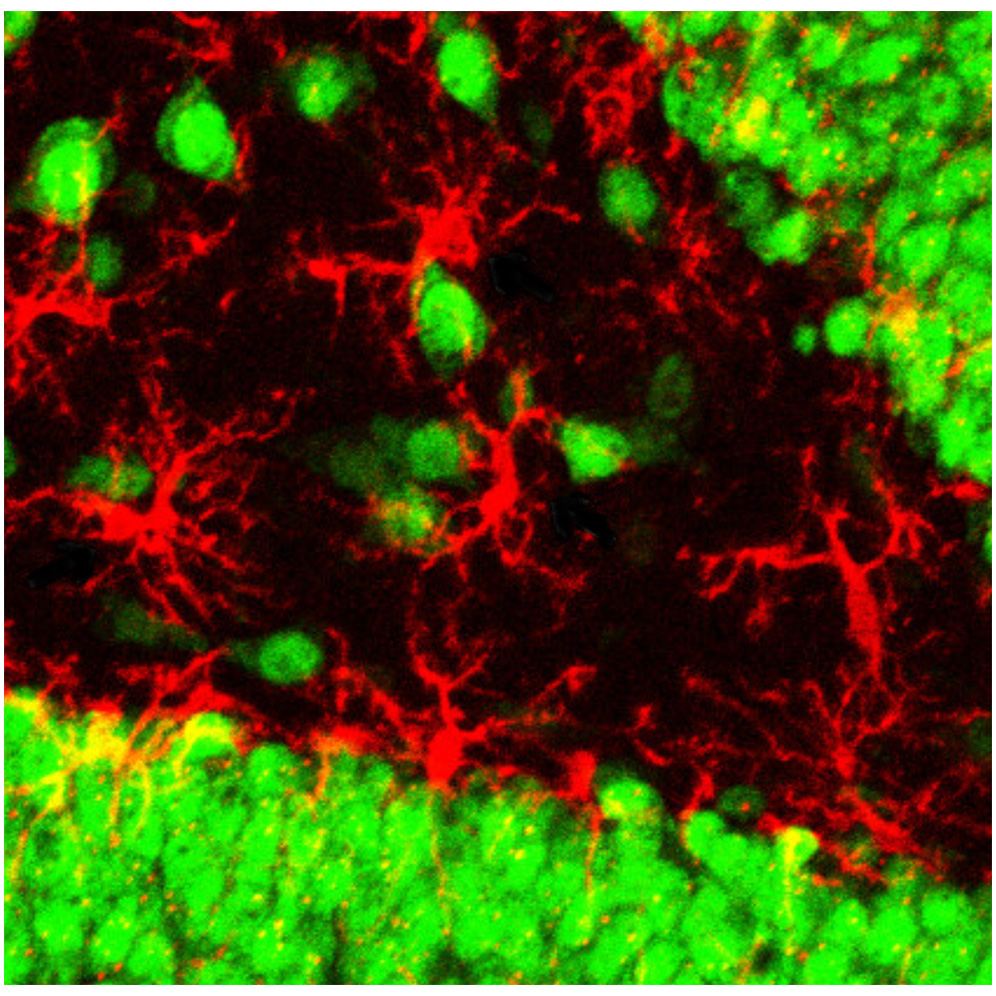

Biomarkers are cellular markers that change upon treatment with a test therapeutic. Quantitative biomarker changes…